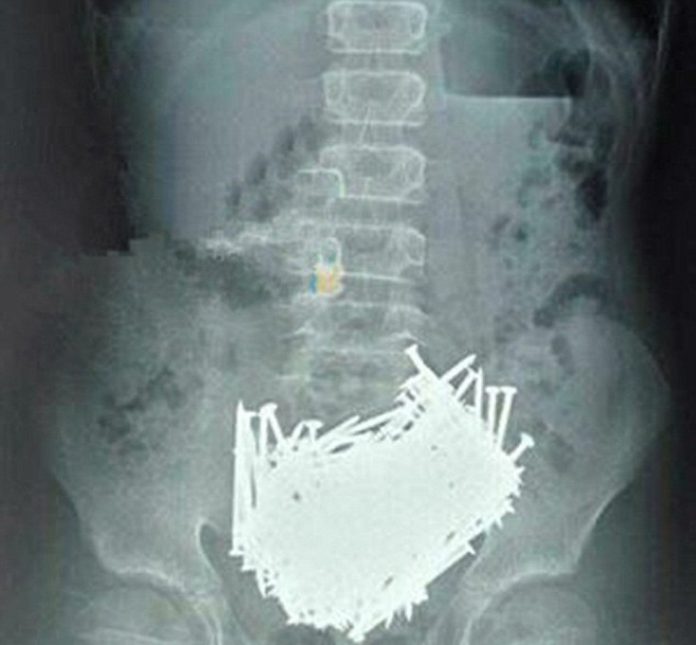

Όταν όμως οι γιατροί έκαναν μια αξονική τομογραφία ρουτίνας για να δουν τι συμβαίνει, ανακάλυψαν ότι το στομάχι του ήταν γεμάτο καρφιά.

Πριν από αυτό ο έφηβος είχε πει στους γονείς του ότι έπασχε από έναν πόνο στο στομάχι ο οποίος φαίνεται ότι επιδεινωνόταν, όπως αναφέρει η People’s Daily Online. Παρόλα αυτά οι γονείς του θεωρούσαν ότι απλώς κρύωσε και πίστευαν ότι θα περάσει. Βλέποντας ότι ο πόνος δεν υποχωρεί, αποφάσισαν να πάνε το γιο τους στο νοσοκομείο όπου οι γιατροί έκαναν μια αξονική τομογραφία. Έκπληκτοι, διαπίστωσαν ότι η κοιλιά του αγοριού ήταν γεμάτη καρφιά.

Τότε ανέλαβαν να κάνουν τη χειρουργική επέμβαση για να αφαιρέσουν πάνω από 200 καρφιά. Παράλληλα, βρήκαν οδοντογλυφίδες, πέτρες και νομίσματα τα οποία ζύγιζαν σχεδόν 7 κιλά!

Το ιατρικό προσωπικού του νοσοκομείου λέει ότι δεν έχει δει κάτι παρόμοιο στο παρελθόν, ενώ ο 15χρονος αργότερα παραδέχτηκε ότι έτρωγε τα καρφιά για περίπου ένα μήνα. Εικάζεται ότι το αγόρι πάσχει από Pica, μια διαταραχή όπου το άτομο έχει επιθυμία να τρώει ξένα αντικείμενα, όπως πέτρες, χρώμα, μέταλλο και γυαλί.